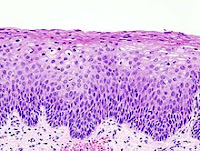

Neoplastik değişiklikler skuamokolumnar bileşkeden (junction) başlar. Serviks kanseri gelişmesinde serviks epitelinde birbiri ardısıra gelen değişiklikler olur, bu da serviks kanserinin erken tanısında önem taşır.

Bu değişiklikler sırasıyla:

1. Normal endoservikal kolumnar epitel

2. Skuamöz metaplazi

3. Hafif-orta-ağır displazi

4. Karsinoma in situ

5. Mikroinvazif karsinom

6. Belirgin invazif karsinom, şeklindedir.

Premalign lezyonların evrelendirilmesi

Preinvaziv servikal hastalık kavramı, 1947 senesinde invaziv kanser görünümüne sahip ancak epitelle sınırlanan epitelial değişiklikler tanımlandığında ortaya atılmıştır. Displazi ve CIS’ın (Karsinoma in situ) sürekli bir olayın farklı basamaklarını teşkil ettiğini düşünen Richart, 1967 yılında servikal intraepitelial neoplazi (CIN I, II, III) terimini tanımlamıştır. Sonraki çalışmalar bu lezyonların tedavi edilmemeleri halinde servikal kansere yol açabileceğini gösterdi. Şimdi ise tedavi edilmediği zaman erken CIN lezyonlarının çoğunun eş zamanlı olarak gerilediği bilinmektedir. Günümüzde anormal lezyonların gelişiminde premalign displastik değişikliklerin değerlendirilmesi için CIN sistemi kullanılmaktadır.

Servikal intraephitelial neoplazi (CIN):

* CIN I Hafif displazi (atipik hücreler epitelin alt 1/3’ünde sınırlı)

* CIN II Orta displazi (atipik hücreler epitelin alttan 2/3’lük kısmında ise)

* CIN III Ağır displazi (epitelin tamamına yakını tutulmuş ise)

* CIS Karsinoma in situ (epitelin tamamı tutulmuşsa)

Not I: CIN I düşük evreli skuamöz intraepitelyal lezyon; CIN II/III yüksek evreli skuamöz intraepitelyal lezyon olarak da isimlendirilir.

Not II: Bütün lezyonlarda bazal membran sağlamdır.

İnvaziv servikal kanserler genellikle uzun bir preinvaziv hastalık evresini izlerler. Mikroskopik olarak, invaziv karsinomlara ilerlemeden önce hücresel atipiden, değişen derecelerde servikal intraepitelyal neoplazilere (CIN) ilerleyen prekürsor lezyonlar spektrumu ile karakterizedir. CIN I lezyonlarının büyük çoğunluğunun geçici olduğu; kısa dönemlerde normale gerilediği veya yüksek derecelere ilerlemediği iyi bilinmektedir. Diğer taraftan, yüksek dereceli (CIN II, III)’ler, her ne kadar bu tür lezyonların da bir kısmı gerilese de, yüksek oranda invaziv kansere ilerleme olasılığı taşır. Servikal öncü lezyonların invaziv kansere ilerlemesinin ortalama 10 ila 20 yıl kadar uzun bir zaman aldığı bilinmektedir.